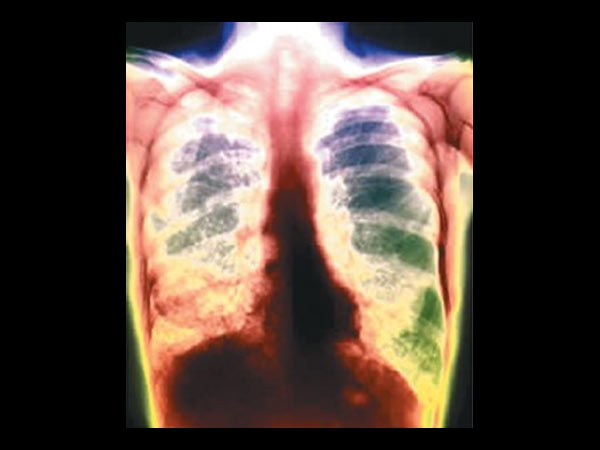

இந்தியாவில் 10 லட்சம் பேருக்கு டிபி!

டெல்லி: இந்தியாவில், 10 லட்சம் பேருக்கு, மிக மோசமான காச நோய் பாதிப்பு ஏற்பட்டுள்ளதாக, உலக சுகாதார நிறுவனம் எச்சரித்துள்ளது.

கடந்தாண்டு மட்டும், இந்தியாவில், 2.7 லட்சம் பேர், இந்த நோய்க்கு பலியாகியுள்ளதாகவும், சுகாதார நிறுவனம் கூறியுள்ளது.

கடந்தாண்டில் மட்டும், 4.5 லட்சம் பேர், புதிதாக இந்த நோயால் பாதிக்கப்பட்டுள்ளனர். இவர்களில் பெரும்பாலானோர், இந்தியா, சீனா, ரஷ்யாவைச் சேர்ந்தவர்கள்.

ஒருவரிடமிருந்து, மற்றவருக்கு, காற்று மூலமாக பரவுவது, காச நோய். இந்த நோயால் பாதிக்கப்பட்டவர்களுக்கு, கடுமையான, தொடர்ச்சியான இருமல், சளி, காய்ச்சல், பசியின்மை, உடல் எடை குறைதல் போன்றவை இருக்கும்.

காசநோய் மரணங்கள்

இந்தியாவில் மட்டும், காசநோயால் மிக மோசமாக பாதிக்கப்பட்டு, கடந்தாண்டில், 2.7 லட்சம் பேர் இறந்து உள்ளனர். காசநோயால் பாதிக்கப்பட்டவர்களில் பெரும்பாலானோர், அதற்கான சிகிச்சையை பெறாமலேயே, இருக்கின்றனர் என்றும், சுகாதார நிறுவனத்தின் ஆய்வு, அடுத்த அதிர்ச்சி குண்டை போட்டுள்ளது.

உலக அளவில்

உலக அளவில்3ல்ஒருவருக்கு காசநோய் பாதிப்பு இருப்பதாக கண்டறியப்பட்டுள்ளது. இந்தியா, தென்ஆப்பிரிக்க நாடுகளில்தான் டிபியினால் அதிக மரணங்கள் நிகழுகின்றன.

இந்தியா, சீனா, தென் ஆப்பிரிக்கா, இந்தோனேசியா மற்றும் பாகிஸ்தான் நாடுகளில்தான் அதிக அளவில் டிபி யினால் பாதிக்கப்பட்டுள்ளனர்.

பெண்கள்-குழந்தைகள்

8.6 மில்லியன் பேர் காசநோயினால் பாதிக்கப்பட்டுள்ள நிலையில் 0.5 மில்லியன் குழந்தைகளும், 2.9 மில்லியன் பெண்களும் இந்த நோயினால் பீடிக்கப்பட்டுள்ளனர்.